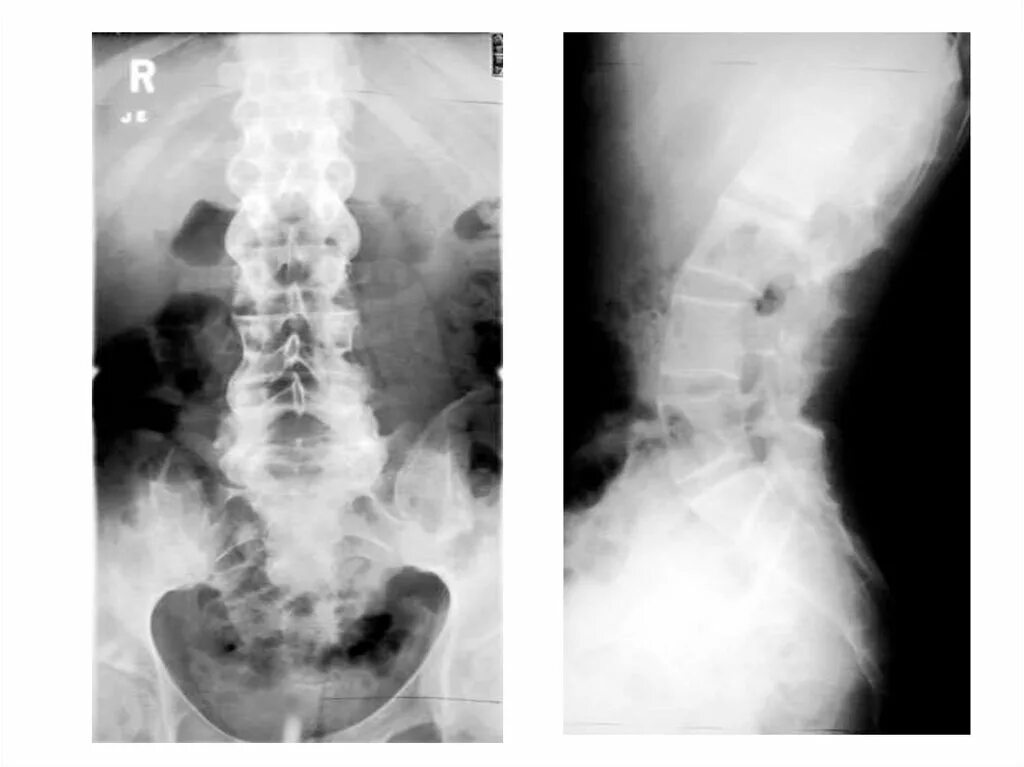

Анкилозирующий спондилоартрит мкб